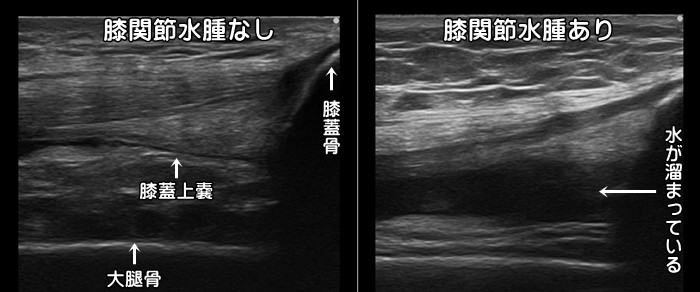

膝関節水腫

膝を曲げるとお皿の周辺が痛い場合は関節の袋(関節包)に水が溜まっている可能性があります。

膝を曲げると袋の中の水は移動するため、膝の裏側や外側など痛みの場所は変化します。